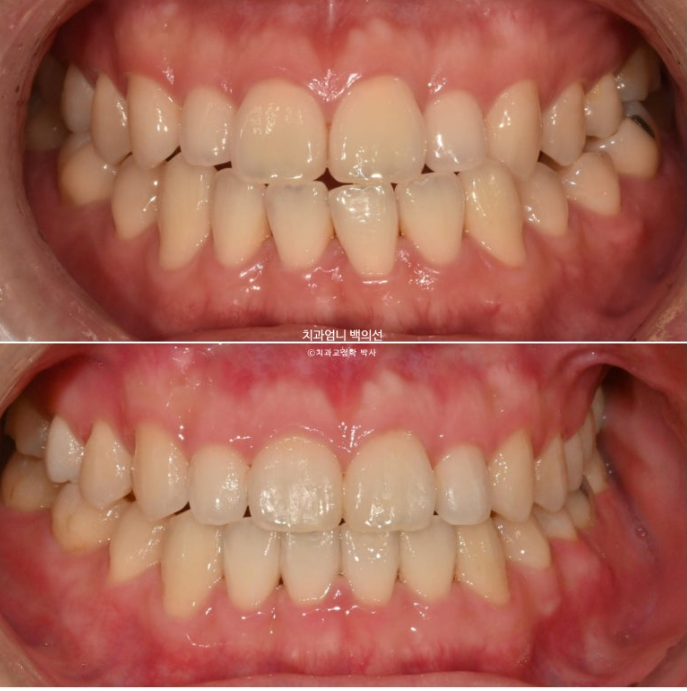

24.01~25.06

배열도 좋습니다

남겨둔 아래 사랑니도 잘 교합되고 있습니다.

이제 전 후 비교해보겠습니다.

아래 전체치열 후방이동으로 아래앞니가 뒤로 들어가며, 결과적으로 아랫입술이 뒤로 들어가며 입술 밸런스가 좋아졌습니다.